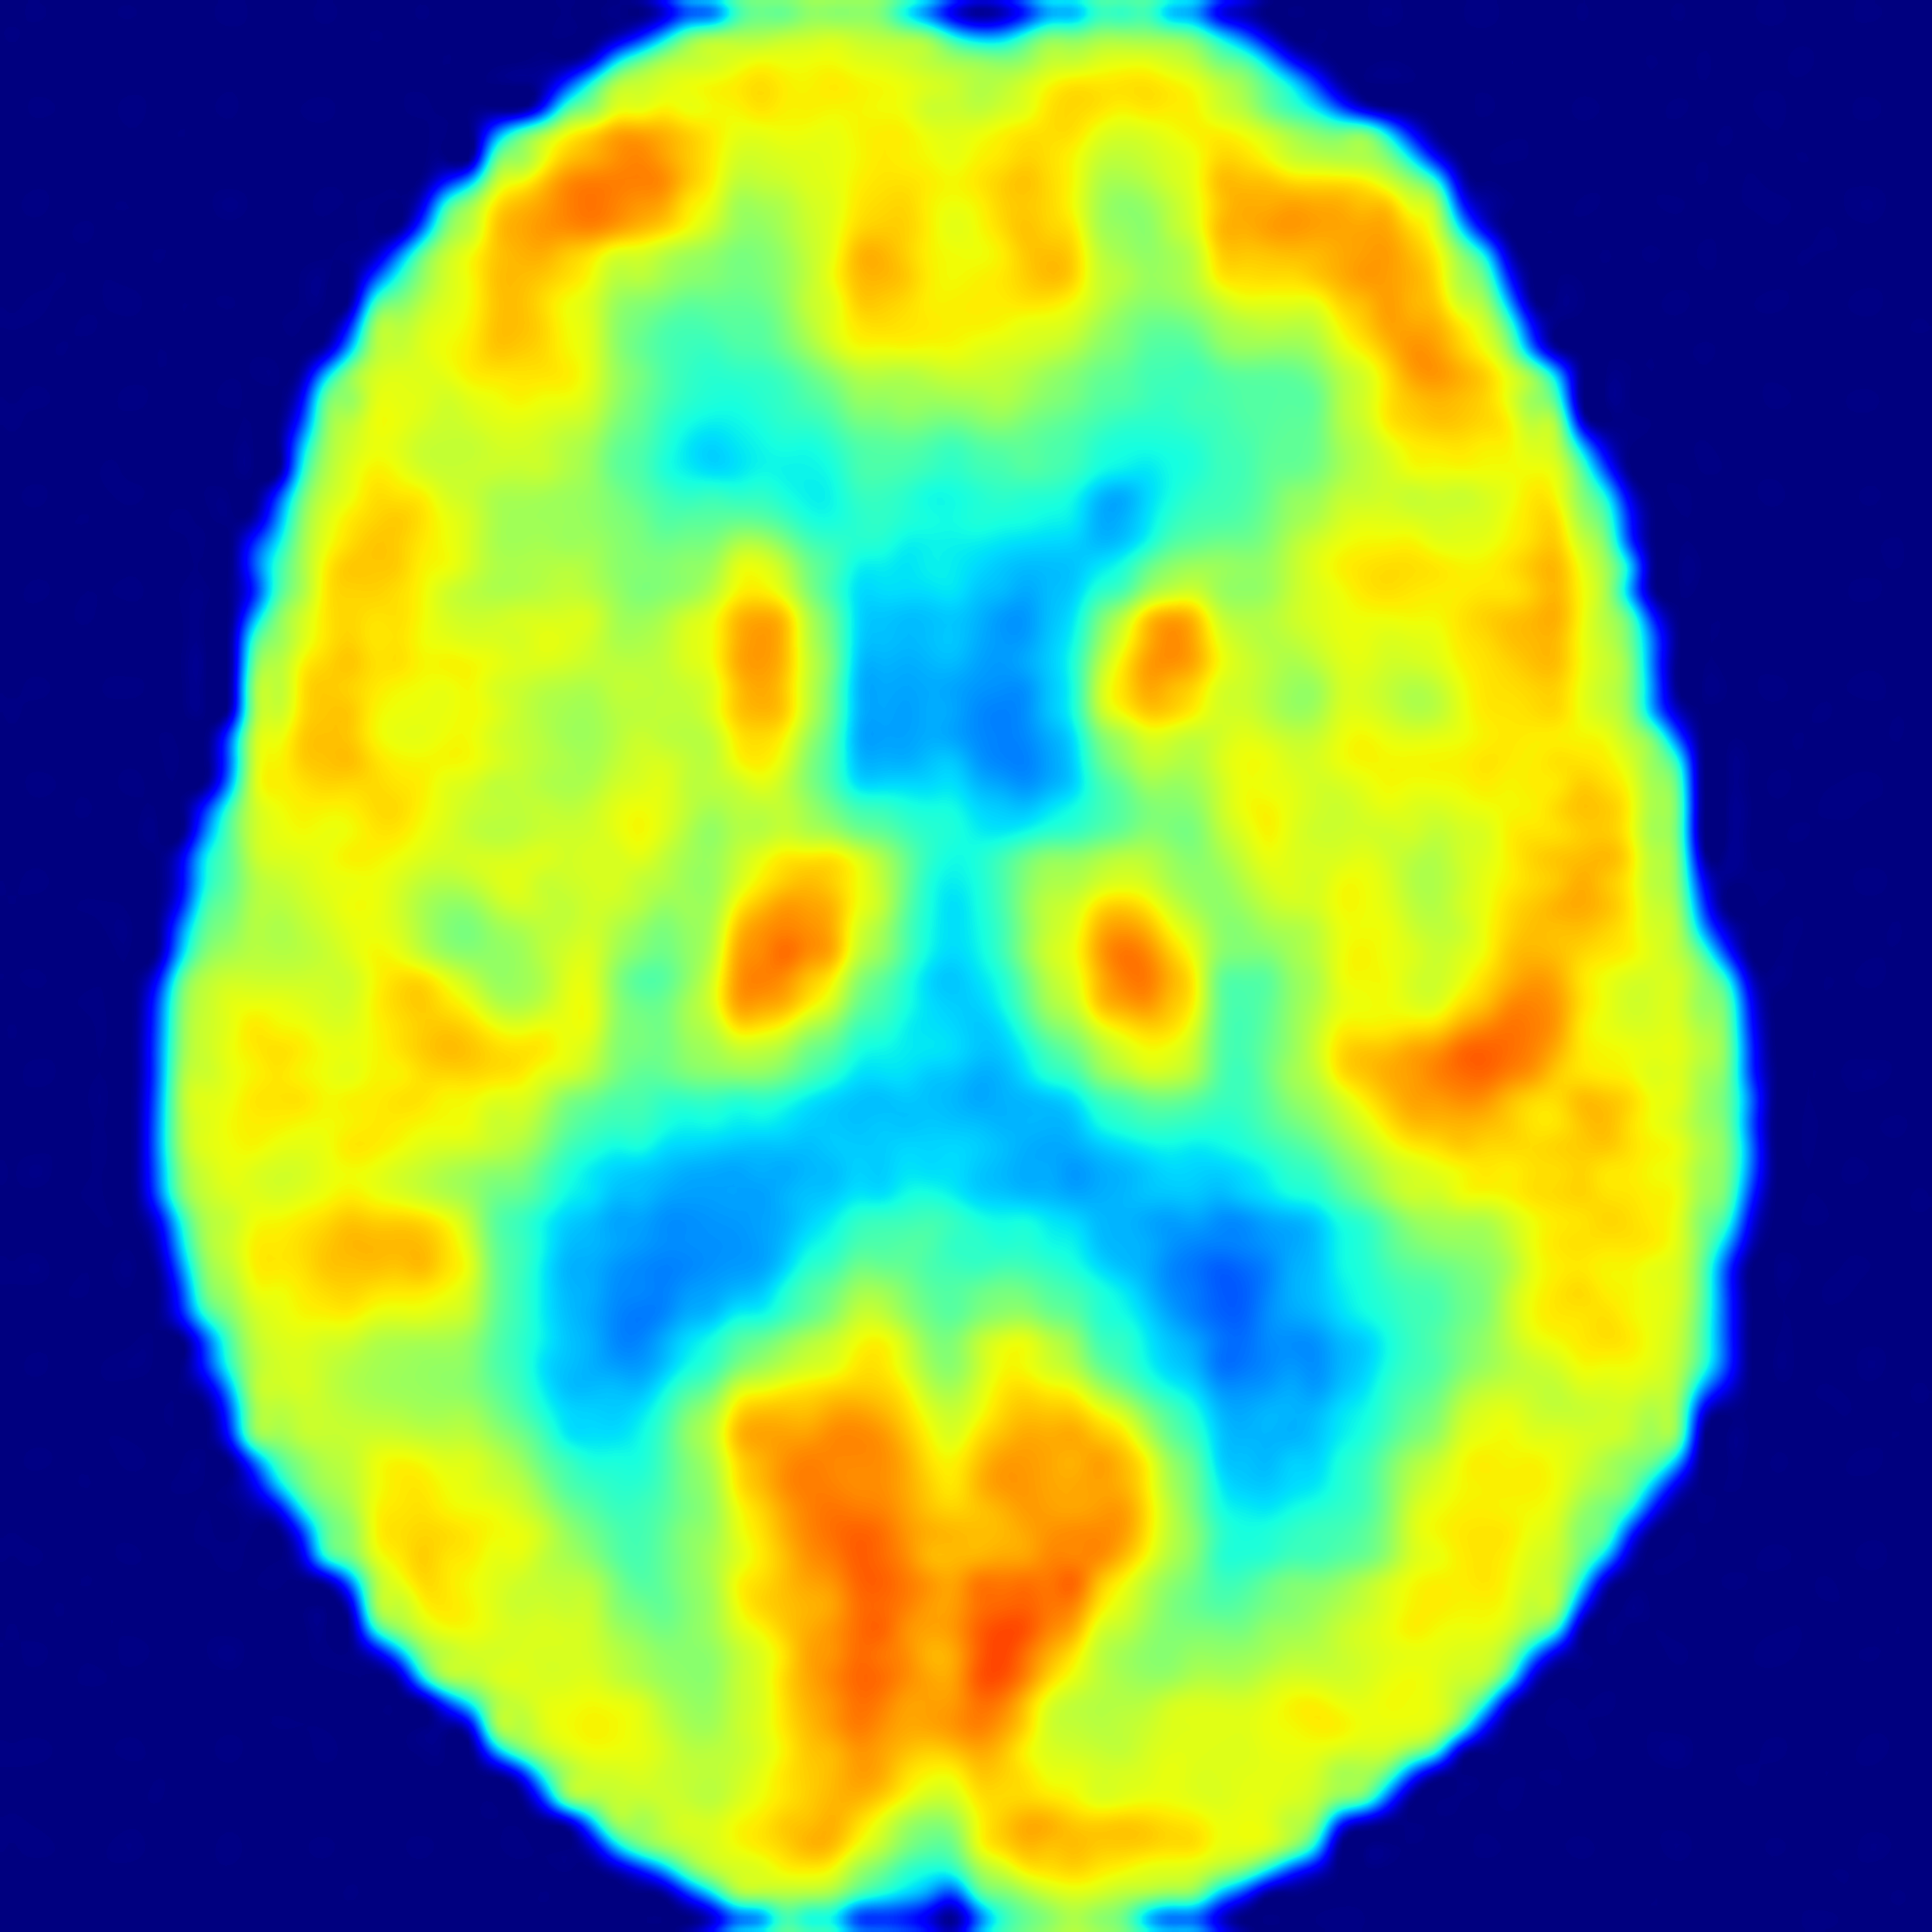

SiM2P simulates PET from MRI with high fidelity

(AD: Alzheimer's Disease, FTD: Frontotemporal Dementia, CN: Normal Control)

82 years old female with AD

66 years old female with AD

71 years old male with FTD

60 years old female with FTD

69 years old female as CN

70 years old male as CN

SiM2P employs a 3D diffusion bridge to simulate PET (SimPET) from structural MRI, conditioned on available auxiliary data. We validated the diagnostic utility of SimPET in a blinded clinical reader study, where SimPET showed significantly higher accuracy than MRI.

In a blinded clinical reader study, SimPET from SiM2P improved diagnostic accuracy by up to 12% over MRI across a range of tasks, with substantially increased interrater reliability.

SiM2P offers high pathological sensitivity even in scenarios where structural MRI lacks sufficient pathological atrophy, such as in early-stage or atypical presentations of AD.

SiM2P with high pathological specificity